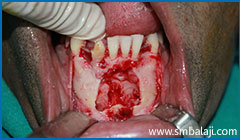

Surgical exposure of impacted teeth

Immediately after surgical removal of impacted lower canine teeth